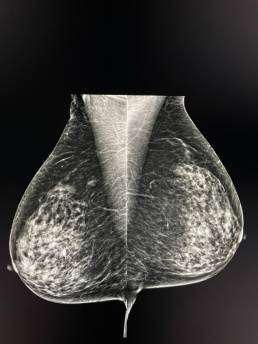

Case of the week (week 15, 2021)

69-year-old woman, screening mammogram.

Stable appearance compared to 2018. Ultrasound didn’t show any suspicious images. MammoScreen® pointed to a right axillary lesion consistent with fibro glandular mass but persistent on spot compression view.

Additional MRI was performed and found a contrast-enhancing mass with irregular contours.

The biopsy was in favor of an infiltrating carcinoma.

MammoScreen can help assess lesions that may be mistaken for lymph nodes.